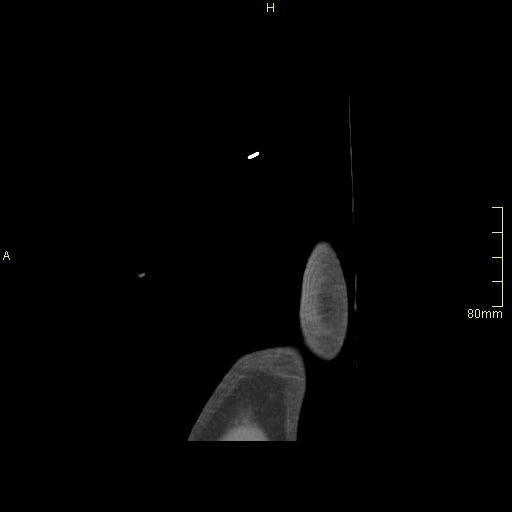

CT Angiography Pelvis - Maximum Intensity Projection (coronal)